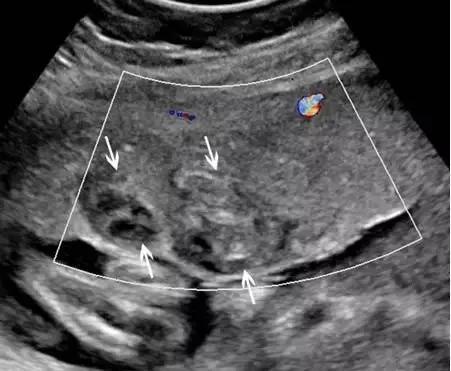

副胎盘是指一个或多个附属胎盘小叶通过血管与主胎盘相连,其发生率在所有妊娠中约占 5%~6%,在高龄孕妇及人工授精时发生率还会高一些。双胎盘是副胎盘的一个变异,其两叶胎盘的大小近似(图 4)。 在超声上,副胎盘表现为两个独立的胎盘通过脐带与主胎盘相连(图 5)

图 5 A 示孕 26 周的胎盘横切面,箭头示 2 个独立的胎盘小叶(长箭头),箭号指示二者之间可见脐带起源于此;图 B 为孕 34 周胎儿死亡后的胎盘大体病理标本,箭头示两个独立的胎盘由源自主胎盘的脐带相连接;该胎儿的死因是由于较大脐膨出导致脐带扭结、脐血管破裂

副胎盘应与一个胎盘附着于宫腔的两个部位相区别。需注意,子宫收缩可形似副胎盘,复查超声即可将二者区别开来。胎儿娩出后,副胎盘可因未被发现而滞留宫腔引起产后出血。副胎盘容易并发血管前置及帆状胎盘。